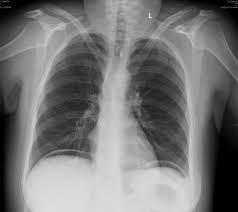

Απλή ακτινογραφία κοιλίας. Σημείο υπερδιαυγαστικού ήπατος (Ευγενική παραχώρηση Dr. V. Penopoulos)